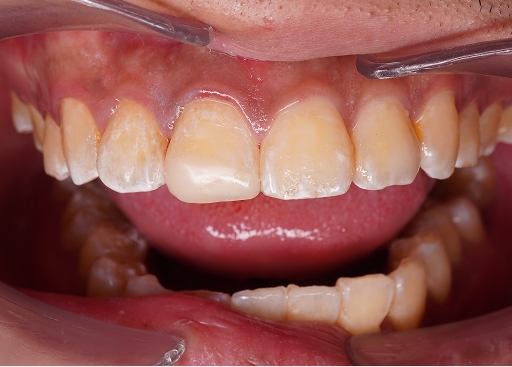

Trigger: When biting down or releasing a bite

Cause: Cracked tooth

We understand how painful and disruptive a toothache can be.

Here’s how we can help relieve your discomfort and address the underlying cause.